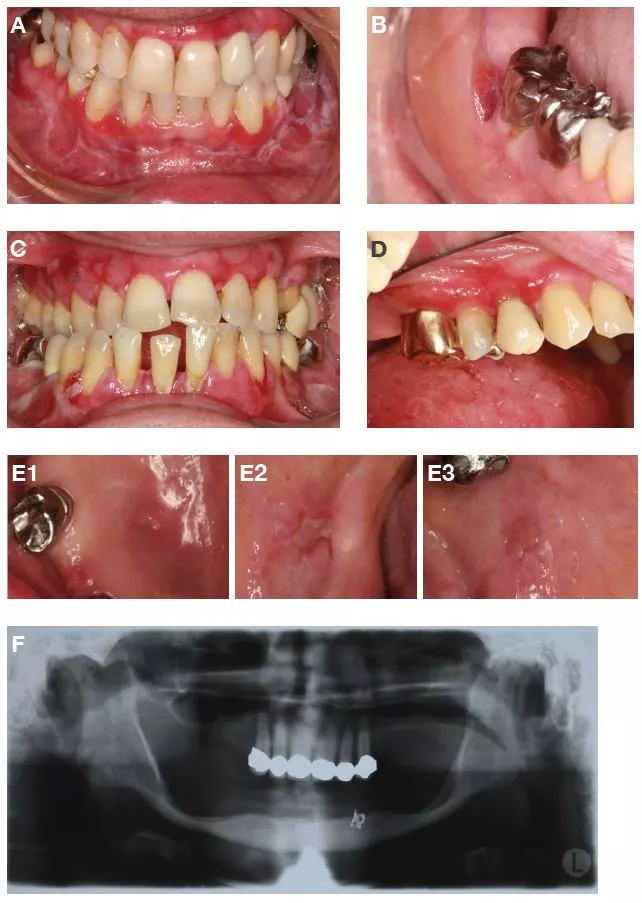

Von 63 Patienten (10,1% der 625 Patienten), bei denen relevante dentale Befunde wie Karies, endodontische oder parodontale Befunde diagnostiziert wurden, hatten 32 Patienten (50,8%) keine weitere relevante dentale oder orofaziale Diagnose, während bei 31 (49,2%) mindestens eine weitere relevante dentale oder orofaziale Diagnose gefunden wurde (meist Funktionsbefunde, orofaziale Erkrankungen und plaquebezogene Befunde). Abbildung 4 zeigt klinische Beispiele für relevante zahnbezogene Symptome.

Dentale Befunde

Abbildung 6 zeigt klinische Beispiele für relevante Verarbeitungsfehler.

Verarbeitungsfehler

Von 45 Patienten (7,2% der 625 Patienten), bei denen relevante Verarbeitungsfehler von FZ oder HZ diagnostiziert wurden, hatten 17 Patienten (37,8%) keine weitere relevante dentale oder orofaziale Diagnose, während 28 (62,2%) mindestens eine weitere relevante dentale oder orofaziale Diagnose aufwiesen (meist mechanische Irritationen, Hyposalivation und plaquebedingte Befunde).

Tabelle 6 fasst alle relevanten Verarbeitungsfehler zusammen, wobei Korrosionsstellen oder Lunker (3,0%), Lötstellen (2,9%) und Perforationen (1,4%) am häufigsten gefunden wurden.